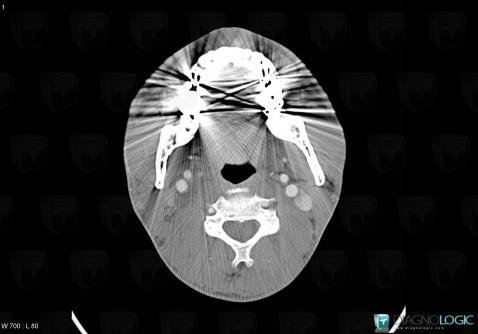

Schwannome, Espaces profonds-cou, Scanner

Voici les informations spécifiques à l'image clé ci dessus:

- Diagnostic Schwannome, Localisation(s) Espaces profonds du cou, comportant les gammes Masse solide cervicale, Lésion de l'espace carotidien